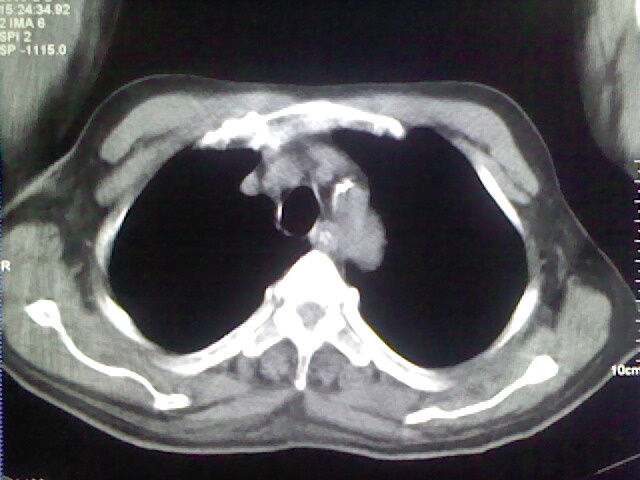

男,70岁,脑出血,长期卧床,左侧背部可触及肿块

慢性间质性炎症,与老年患者长期卧床相关,胸壁软组织及肋骨未见异常。

肺部感染,背部筋膜增厚,考虑坠积性水肿或炎症

右侧肺部见片状密度增高影,边缘模糊。考虑炎症。另食管壁增厚。